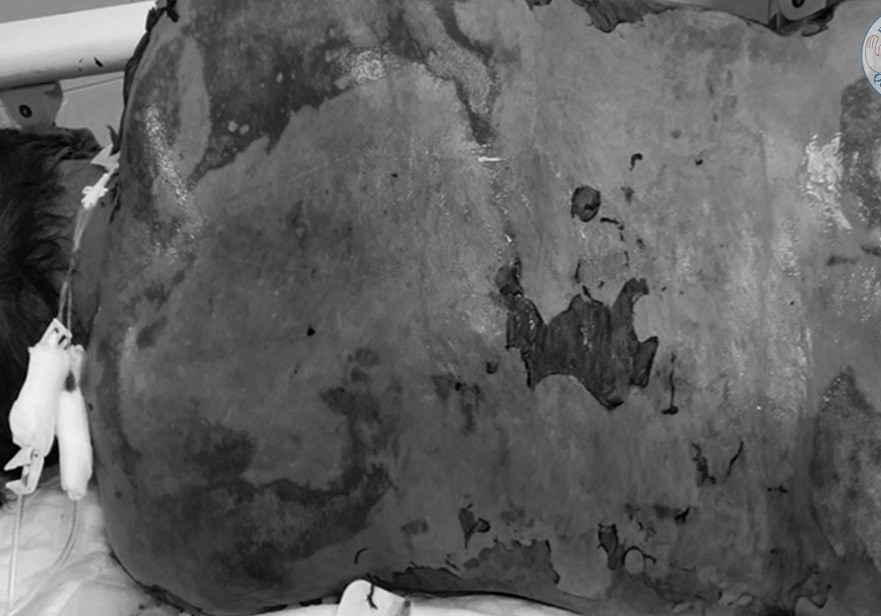

Đầu tiên là bệnh nhân N.V.H. (71 tuổi), nhập viện ngày 20/4 với triệu chứng ngứa, nổi mẩn đỏ hết vùng đầu và mặt, sốt cao (39-40 độ C).

Người này được điều trị sốt tại khoa nội, sau đó tình trạng da bị rộp, bong tróc ngày càng nặng, lan hết khắp cơ thể kèm tổn thương mắt, miệng, cơ quan sinh dục. Bệnh nhân được chỉ định chuyển qua khoa Hồi sức tích cực chống độc (ICU) để điều trị tiếp.

Với bệnh nhân như ông H., tình trạng tổn thương da khắp cơ thể nên cần khoảng 5 người để tắm rửa và thay băng hàng ngày. Điều dưỡng cố gắng bằng nhiều cách để giảm đau đớn cho người bệnh như chích thuốc giảm đau, động viên tinh thần.

Ca thứ hai là bệnh nhân N.T.N.C. (47 tuổi) có hoàn cảnh rất khó khăn. Vùng da bị mất thượng bì cần phải có băng gạc không dính để đắp lên vết thương, ngăn ngừa nhiễm khuẩn. Bệnh viện phải liên hệ tuyến trên để xin những miếng băng gạc chuyên dụng đắp cho bệnh nhân.